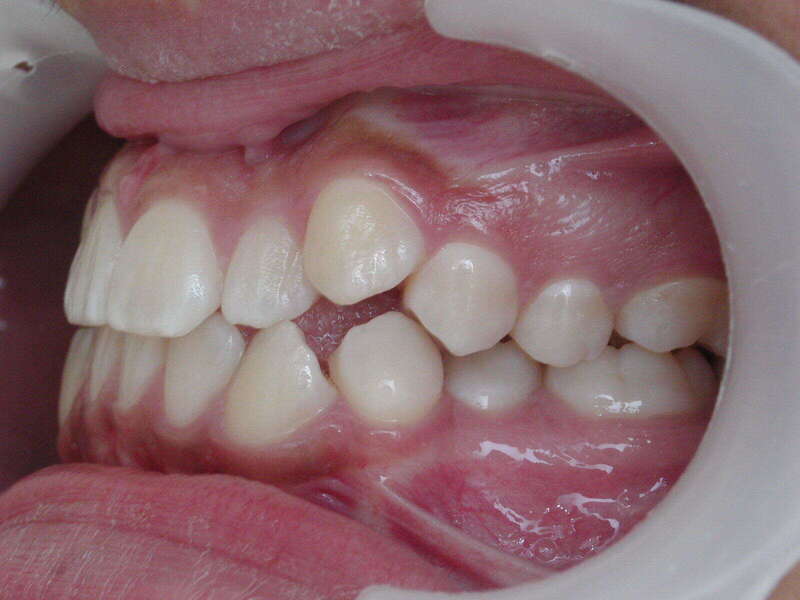

Cas n°2 traité par aligneurs - adolescent

Ce cas d'une adolescente illustre la puissance des aligneurs dans la correction d'une Classe II sévère sans extraction. La stratégie a reposé sur une distalisation séquentielle de l'arcade supérieure, soutenue par une coopération soutenue du port d'élastiques intermaxillaires.

Cette approche a permis d'annuler un surplomb incisif (overjet) important tout en réhabilitant une occlusion de Classe I stable. L'absence d'extraction a été déterminante pour préserver l'harmonie du profil, évitant le creusement du visage souvent lié aux traitements soustractifs classiques.

Résultats clés :

• Conservation dentaire : Alignement total sans perte de prémolaires.

• Fonctionnalité : Engrènement parfait et stable.

• Esthétique faciale : Soutien labial optimal et sourire élargi.

C'est une démonstration claire de l'orthodontie moderne : efficace, esthétique et respectueuse de l'anatomie naturelle.